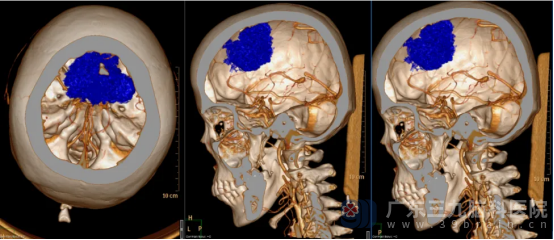

我院神经外五科学科带头人鲁明接诊患者后,根据影像资料,发现患者双侧额顶部镰旁占位性病变,大小约63mm×45mm×44mm,考虑肿瘤性病变,头颅CTA检查提示肿瘤供血极其丰富。神经外五科副主任卢建侃迅速邀请多学科专家会诊,初步判断病变可能为脑膜瘤,需尽快手术干预。

▲术前影像资料